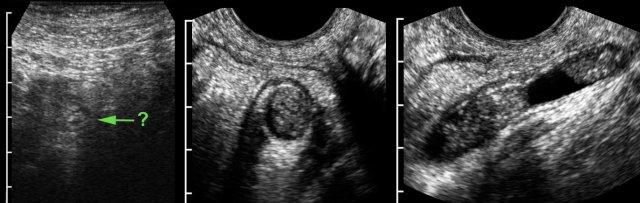

Bệnh Crohn

Bệnh nhân nữ trẻ, mang thai 4 tuần, nhập viện vì đau hố chậu phải kéo dài 6 ngày và CRP 120.

Siêu âm phát hiện thành hồi tràng đoạn cuối dày lên với những thay đổi giảm âm ở lớp dưới niêm mạc, nghi ngờ bệnh Crohn.

TVUS bổ sung phát hiện một ổ áp-xe (a.) được bao bọc bởi lớp mỡ mạc treo và mạc nối (*).

Áp-xe vùng chậu sâu

Bệnh nhân nữ trẻ, đau bụng và sốt 10 ngày sau phẫu thuật vì viêm ruột thừa thủng.

CT cho thấy ổ tụ mủ hai thùy, nằm sát thành trực tràng dày, lòng rỗng (R.).

TVUS xác nhận ổ áp-xe và phát hiện một đường hầm giảm âm (*) từ ổ áp-xe thông vào lòng trực tràng (R.), kèm theo xóa mờ khu trú cấu trúc các lớp thành trực tràng đang phù nề.

Những dấu hiệu TVUS này, kết hợp với tình trạng lâm sàng của bệnh nhân đang cải thiện, là dấu hiệu của quá trình tự thoát lưu sắp xảy ra.

Ba ngày sau, ổ áp-xe thành dày gần như đã rỗng hoàn toàn.

Bệnh nhân hồi phục mà không cần dẫn lưu bằng phẫu thuật hay can thiệp dưới hướng dẫn hình ảnh.